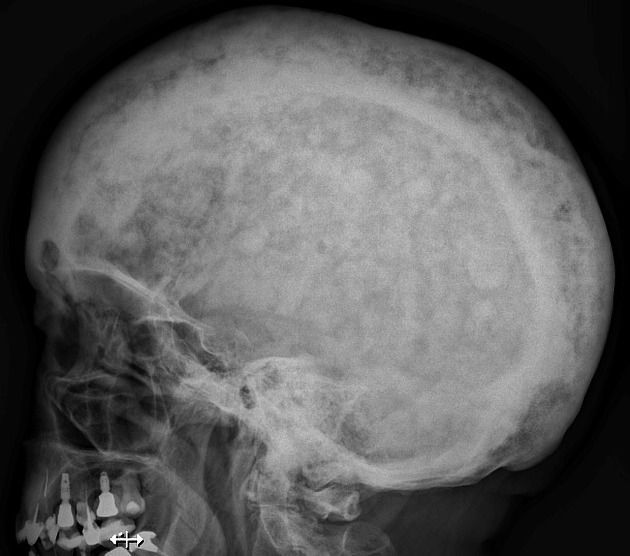

Cotton wool appearance of the skull is attributed to Paget's disease. The characteristic radiological finding arises due to thickened and disorganized trabeculae due to increased bone turn-over. Areas of sclerosis are also visible. Reference: https://radiopaedia.org/articles/cotton-wool-appearance-bone Image via: https://radiopaedia.org/articles/cotton-wool-appearance-bone